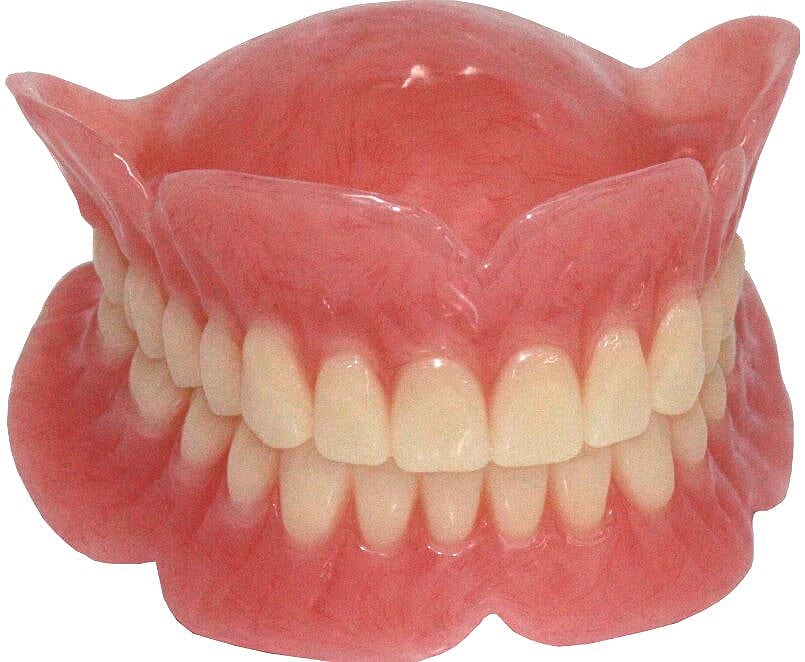

In the long term, implants are aesthetic, functional and comfortable. Gums and bone can recede around a fixed bridge or removable partial denture, leaving a visible defect. Resorbed bone beneath bridges or removable partial dentures can lead to a collapsed, unattractive smile. The cement holding bridges in place can wash out, allowing bacteria to decay teeth that anchor the bridge. In addition, removable partial dentures can move around in the mouth and reduce your ability to eat certain foods.